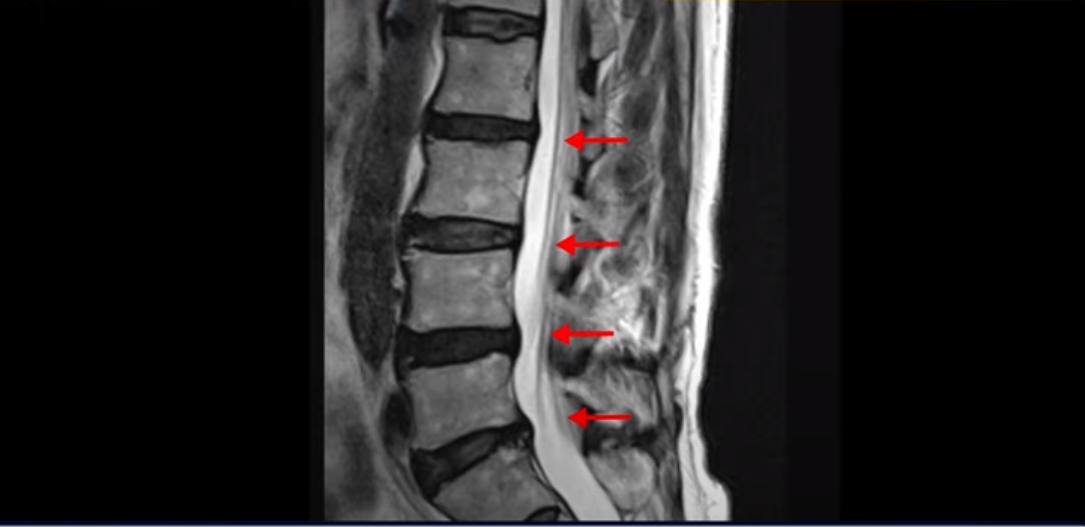

이 환자분 MRI 보면서 설명 드린 후 왜 이런 환자는 신경주사가 효과가 없는지 왜 근육재활치료를 꼭 받아야 하는지, 근육재활치료로 어떻게 좋아질 수 있는지 설명 드리도록 하겠습니다. 이분MRI를 보면 허리 여러 마디 퇴행이 진행되어 있고 디스크와 협착도 있지만 아주 심해 보이지는 않습니다.

이분 다리는 양쪽이 다 아픈데 양쪽 추공간이 좁아져 있긴 하지만 여전히 하얀 지방이 많이 보이는 상태로 심하게 좁아 보이지는 않습니다.

척추관이 가장 좁아진 4번 5번을 보면 중심성 협착이 있지만 많이 심하지는 않습니다